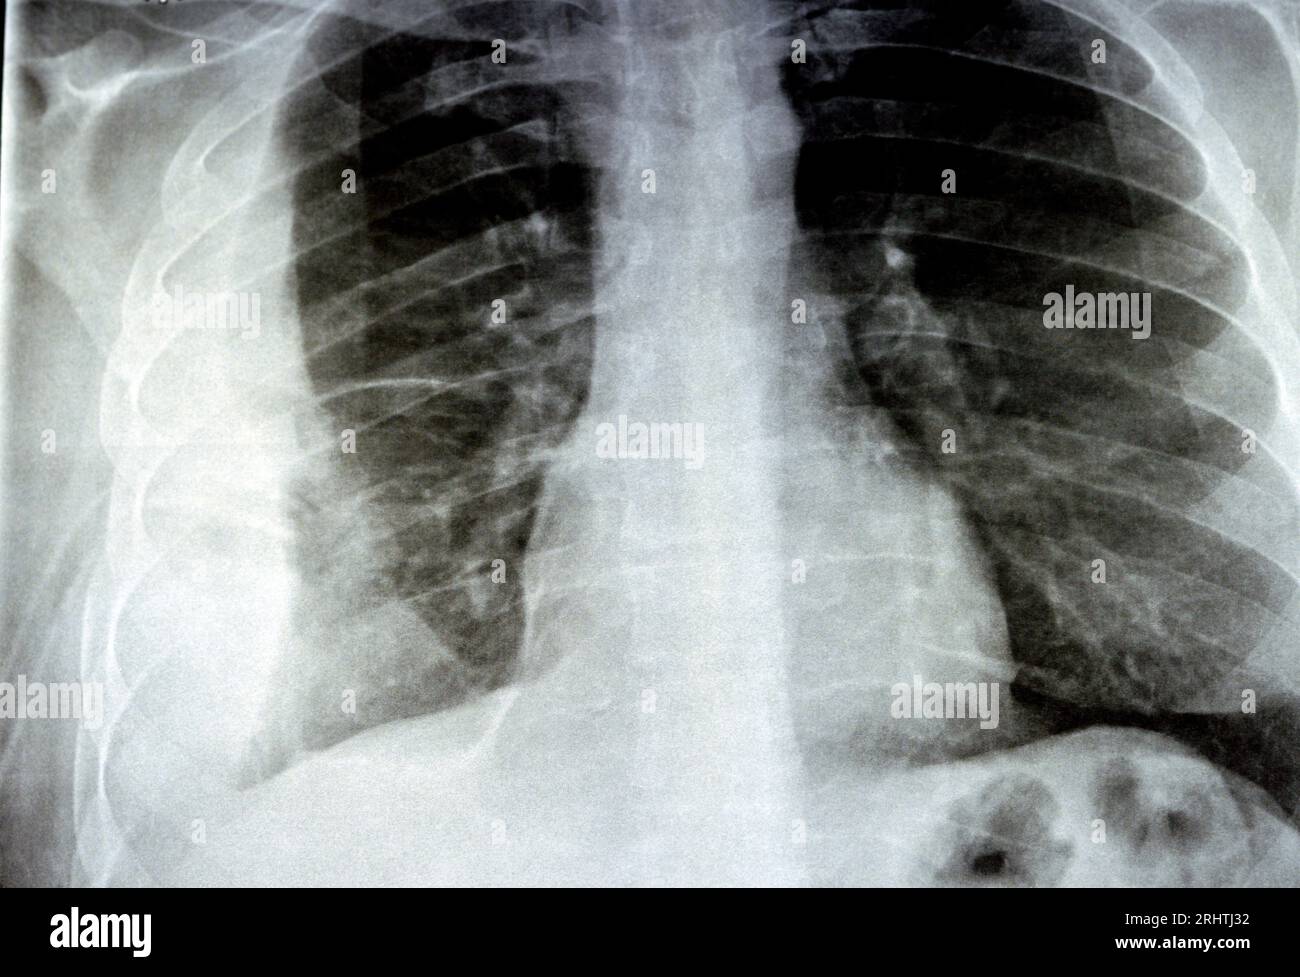

SOLVEDChest xray Consolidation in the right lower lobe Moderate

Plain X ray for a patient with aspiration pneumonia right lung, empyema Aspiration Of Lung Fluid   pleural aspiration to treat a pleural effusion.   thoracentesis is a procedure in which a doctor uses a needle and catheter to remove excess fluid from the space between your lungs and.  thoracentesis is needle aspiration of fluid from a pleural effusion. This space is called the pleural space or cavity. A pleural aspiration is a simple procedure. Aspiration Of Lung Fluid.